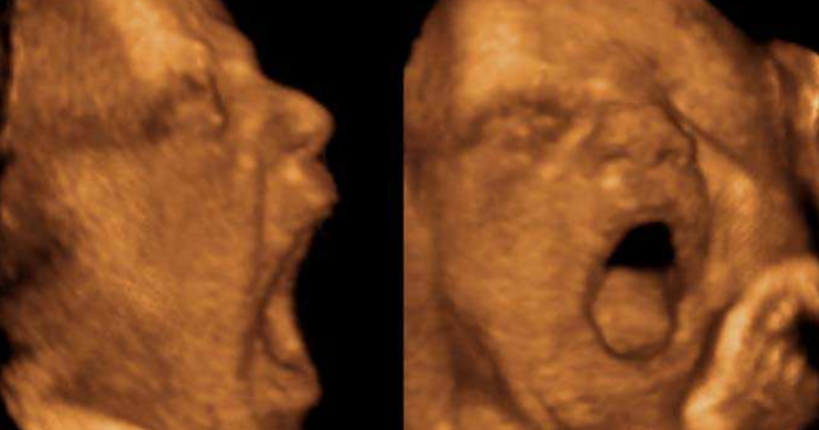

Ph. credits: Olivier Walusinski (2012) Fetal Yawning, Sonography, Dr. Kerry Thoirs (Ed.), ISBN: 97

Ecografie 4D e analisi frame per frame: come è stato studiato lo sbadiglio fetale

La ricerca ha coinvolto 32 feti sani, osservati tra la 23ª e la 31ª settimana di gestazione presso l’Azienda Ospedaliera di Padova. I video ecografici 4D sono stati analizzati frame per frame presso l’Early Infancy Lab dell’Università di Ferrara utilizzando il System for Coding Perinatal Behavior (SCPB), basato sul Baby Facial Action Coding System (Baby FACS). Questo metodo permette di distinguere in modo rigoroso tra veri sbadigli e altre aperture della bocca, un passaggio metodologico cruciale per evitare sovrastime.